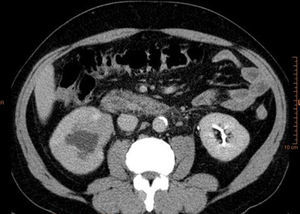

En la TAC aportada se apreciaba una ectasia pieloureteral derecha grado ii/iv, producida por una lesión polipoidea en la pelvis renal que se extendía al uréter proximal, así como lesiones hepáticas (figs. 1-3). La citología urinaria era negativa para células neoplásicas, y la cistoscopia no reveló la presencia de lesión vesical concominante.

Tras un año de tratamiento el enfermo presenta buena respuesta al tratamiento, mostrando mínimos restos de su enfermedad al nivel del uréter proximal (fig. 6).